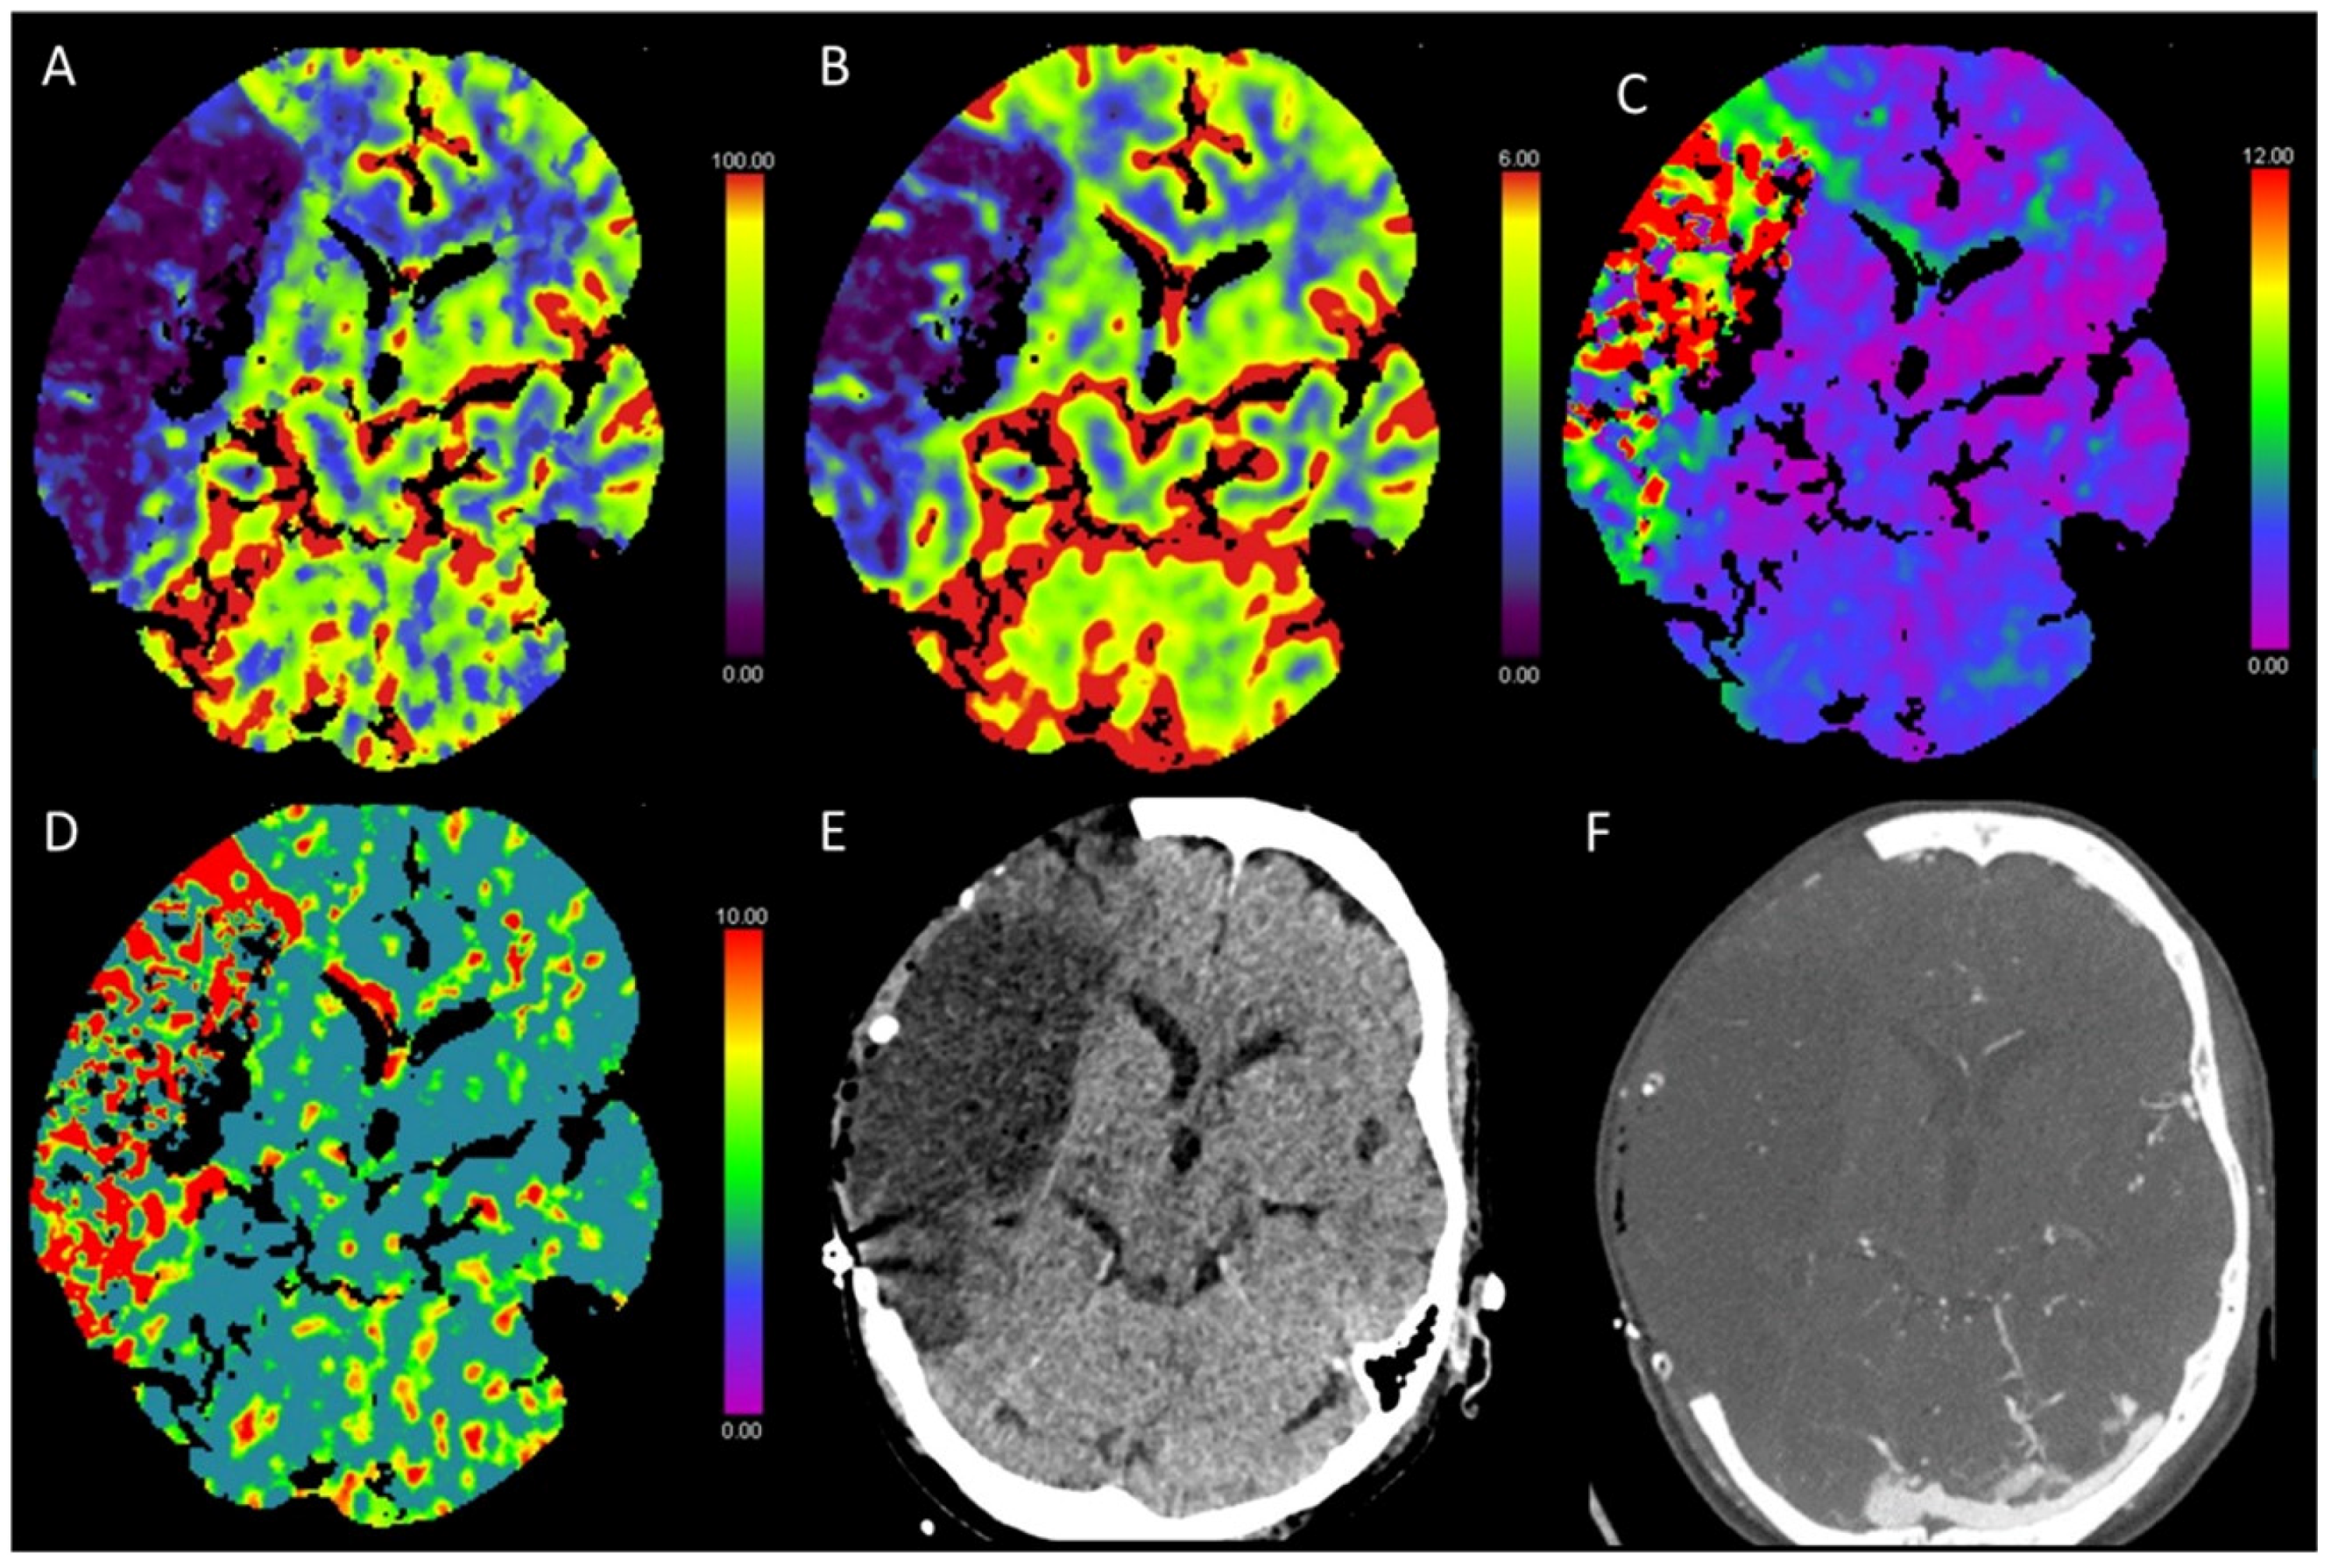

3.3. Global Hypoxic-Ischemic Injury/Brain Death

3.4. Variation in Cerebrovascular Anatomy